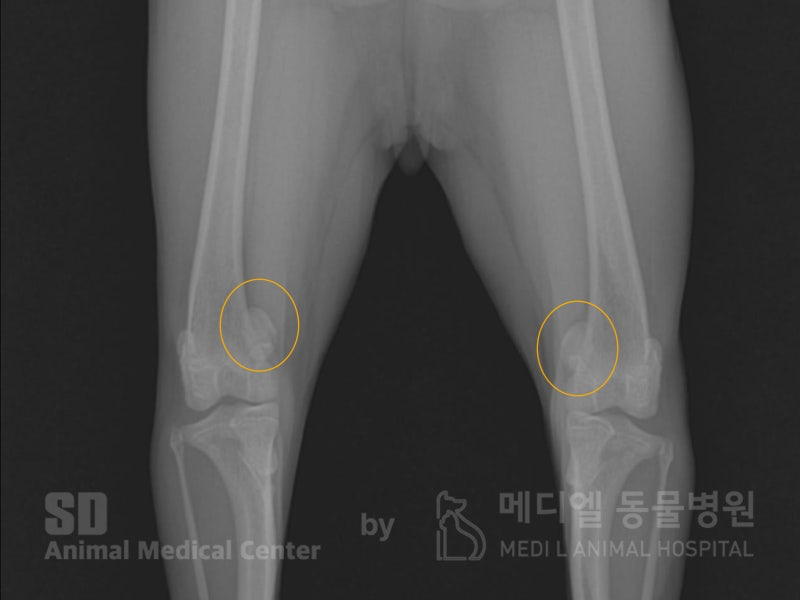

병원에서 촬영 방사선 사진입니다. 정상위치(무릎의 중간)에 있어야 할 슬개골이 안쪽으로 빠져있는게 확인됩니다.

이럴 경우 내측성 슬개골 탈구로 진단되며, 방치하게 될 경우 관절염이나, 전십자인대단열까지도 진행될 수 있습니다.

어린 나이일지라도, 걸음걸이가 이상하다면 병원으로 내원해주세요.